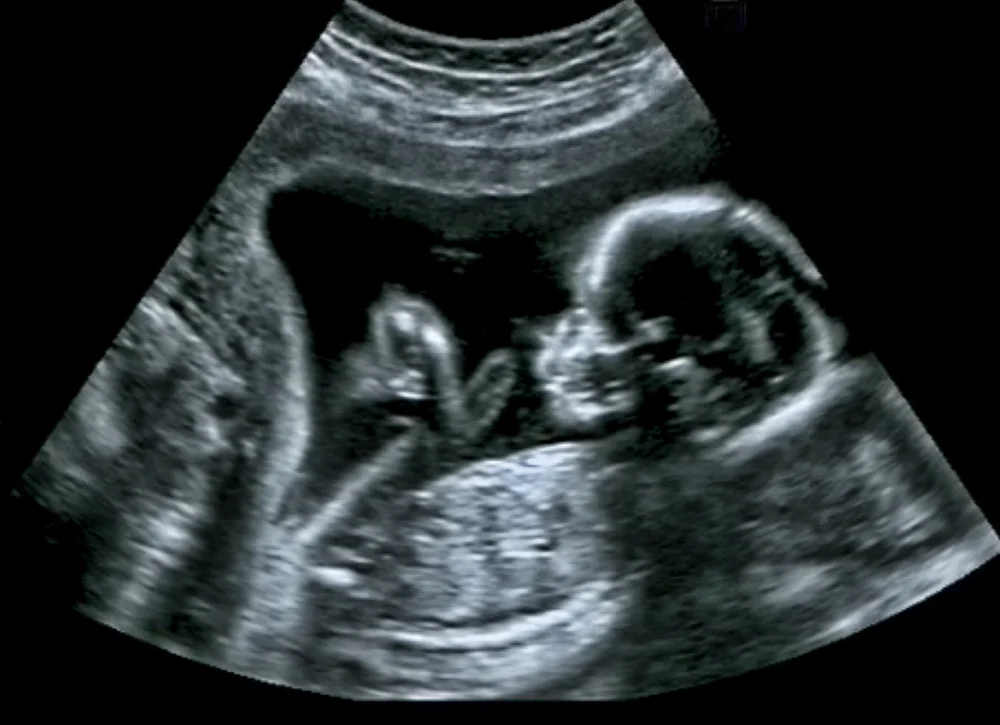

הריון היא בשורה מרגשת ומשמחת. לצד השמחה הגדולה ישנם גם לא מעט חששות מהתהליך אותו צפוי הגוף לעבור בתשעת החודשים הקרובים, בעיקר עבור מי שזה ההיריון הראשון שלה והיא איננה יודעת לקראת מה היא הולכת ומה היא צפויה לחוש. רגע לפני שאת נכנסת ללחץ, שבי על הספה, שתי מים והירגעי! את לא לבד אף פעם ומובטח לך כי בסוף ההליך כל תופעות הלוואי שתחושי ישתלמו בהחלט. בשליש הראשון ההיריון משתרש בדופן הרחם והעובר מתחיל אט אט להתפתח. מערכות גופו ואיבריו של העובר מתחילות להבנות מתחילת ההיריון ועד לשבוע ה- 14 וזהו זמן רגיש עבור שניכם.

בתחילת ההיריון ישנן תופעות פיזיות רבות הקורות בתוך הגוף. חלק מהן מורגשות וחלקן פחות. בכל מקרה אם את מרגישה את התסמינים הבאים דעי שזה לגיטימי לחלוטין: כאבי בטן תחתונה, עלייה בחום הגוף, הפרשות נרתיקיות שונות מהרגיל, בטן נפוחה, בחילות, עייפות ותשישות, סחרחורות וכאבי ראש, מצבי רוח משתנים, טעמים מוזרים ותשוקה למזונות מסוימים, תיאבון רב או חוסר תיאבון, רגישות לריחות וחוש ריח מפותח מהרגיל, הטלת מים מרובה, עצבנות, תנועות עובר ועוד.